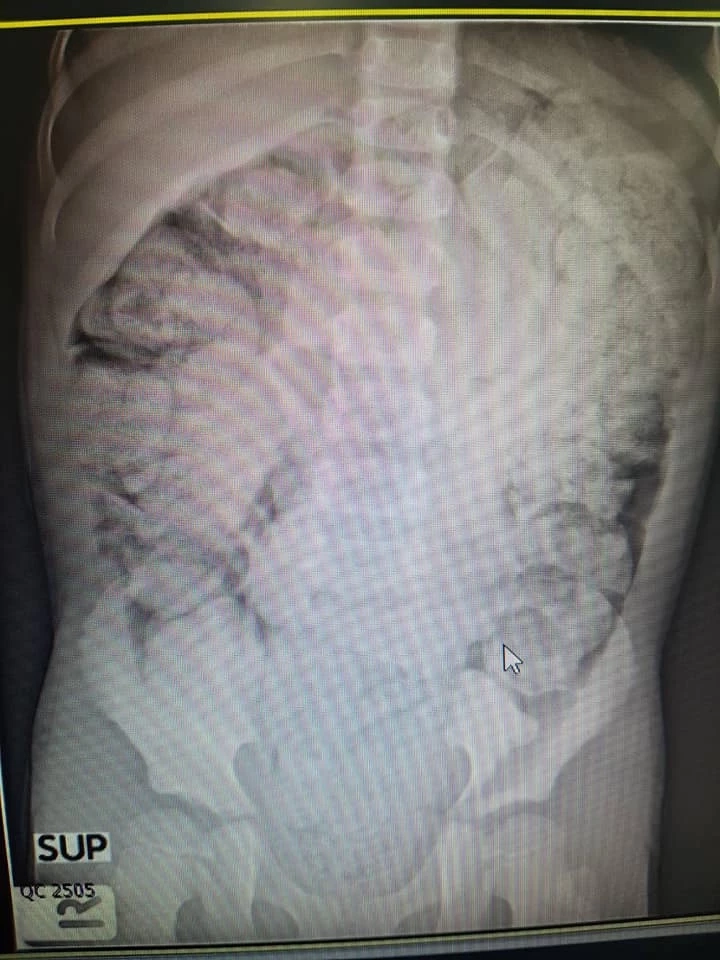

เรียกว่าสร้างความฮือฮาและตื่นตัวจากบรรดาชาวเน็ตเป็นอย่างมาก หลังจากที่ "ตุ๊กตา จมาพร แสงทอง" นักร้องสาวจากเวทีเดอะวอยซ์ ซีซั่น 2 ได้โพสต์เฟซบุ๊ก Jamaporn Saengthong เปิดเผยว่า ตนป่วยเป็น “โรคขี้เต็มท้อง” จนต้องเข้าพบแพทย์เพื่อเข้ารับการรักษา ระบายอุจจาระที่คั่งค้างอยู่ในท้องและลำไส้

เอาจริงๆ ฟังชื่อโรคมันก็ดูน่าตลกอยู่หรอกนะ แต่คนที่เป็นจริงๆ คงไม่ตลกด้วยสักเท่าไร เพราะอาการมันช่างทรมานเหลือเกิน เนื่องจากเราไม่สามารถขับอุจจาระออกไปได้หมด ว่าง่ายๆ มันก็คืออาการท้องผูกประเภทหนึ่งนั่นแหละ

คืองี้ ปกติแล้วในลำไส้ใหญ่เราเนี่ยมันจะมีหน้าที่ดูดซึมน้ำออกไปด้วย คนไหนที่ท้องผูกบ่อย หรืออั้นขรี้ไว้นานๆ 3-4 วันถ่ายรอบนึง ก็ทำให้อุจจาระไปติดค้างอยู่ตามผนังลำไส้ มันถูกดูดน้ำออกไปเรื่อยๆ จนในที่สุดจากของเหลวก็กลายเป็นของแข็งแทนได้ พอแข็งมากๆ ก็ทำให้เราตุ่ยลำบากเป็นคอมโบ้ต่อเนื่องของอาการนี้นั่นเอง

แน่นอนว่าถึงแม้จะกินข้าวเข้าไปเพิ่ม มีของล็อตใหม่เข้ามาเติม แต่ตรงปลายลำไส้ที่มันแข็งแล้ว และไม่ยอมตุ่ยออก ของใหม่ก็จะไปกองอยู่บนๆ และสะสมกองต่อไปเรื่อยๆ (ยกเว้นกรณีของใหม่ที่มันเป็นของเหลวก็อาจแทรกตัวออกไปลงโถได้ก่อน) ยิ่งปล่อยไว้นานข้างล่างก็จะยิ่งแข็ง แล้วก็จะยิ่งถ่ายยากขึ้นเป็นเงาตามตัว